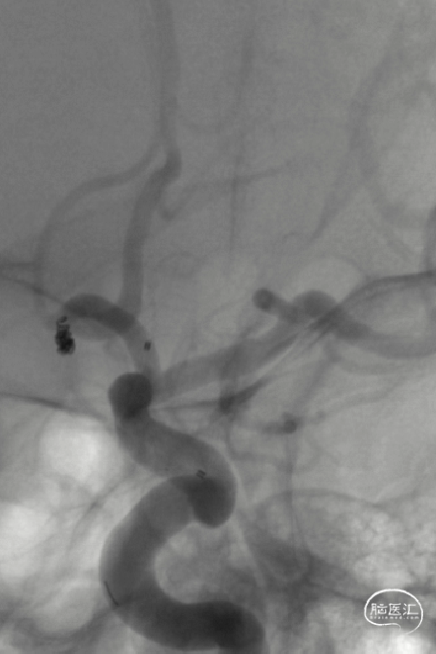

影像信息

前交通微小动脉瘤,伴多个子囊

尺寸:1.6*2.1mm

患者右侧大脑前动脉发育纤细